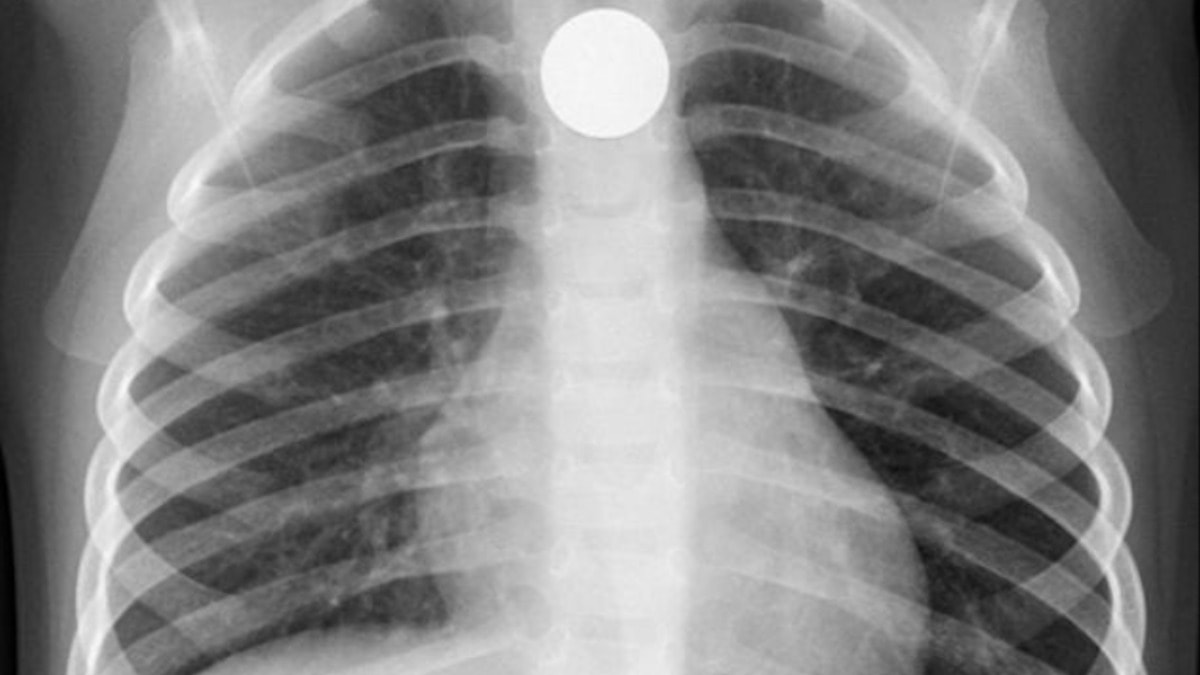

Değeri 33 bin 585 Yeni Zelanda doları (806 bin TL) olan 'Fabergé yumurtası' biçimindeki kolye, hala adamın karnının içinde.